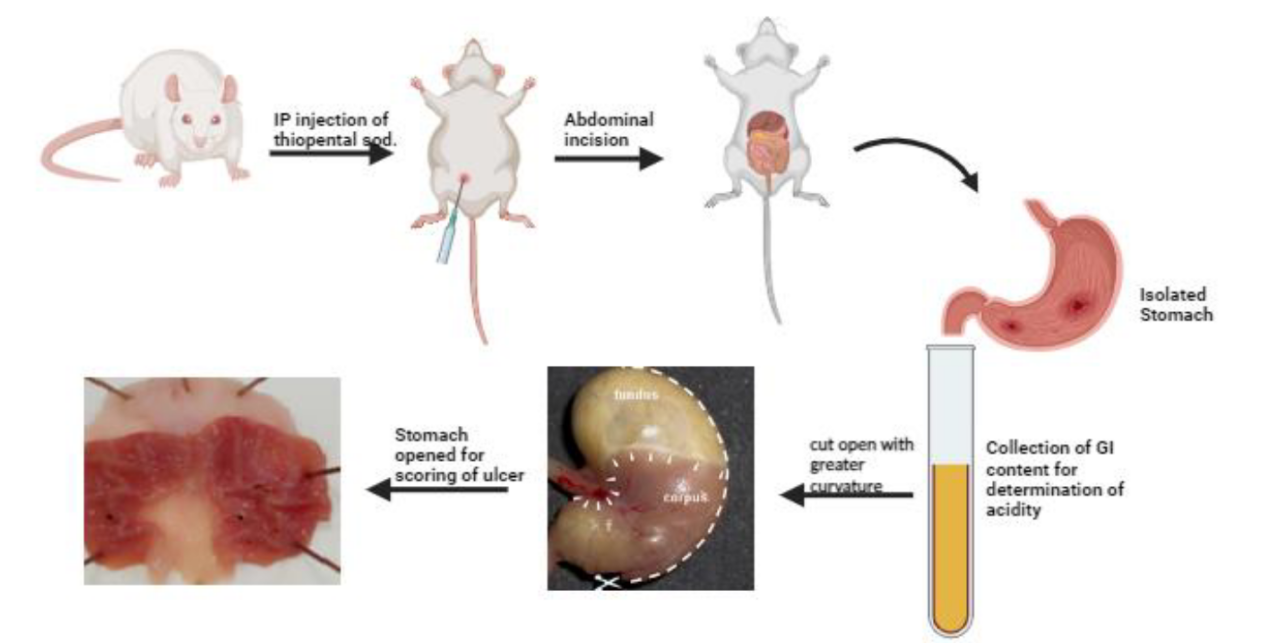

- 处死与取胃:在灌胃后预定的时间点(如大鼠1小时后,小鼠30~60分钟后),通过颈椎脱臼法或其他合适的方法处死动物。然后迅速剖腹,结扎幽门和贲门,以防止胃内容物外溢。

- 胃组织固定与清洗:从动物体内取出胃后,立即注入甲醛溶液进行固定。固定时间一般为30分钟至1小时。之后沿胃大弯剪开胃壁,外翻胃组织,倒去内容物,并用生理盐水轻轻冲洗去胃内残渣。

- 观察与记录:在解剖显微镜下观察胃黏膜的溃疡损伤程度。溃疡长度大于1mm者测其长度,每1mm计为1分;宽度大于1mm者则计分加倍;若为小溃疡点计0.5分。将计分相加即为该动物的溃疡指数。

损伤评估:宏观观察胃黏膜出血、糜烂灶,计算溃疡指数(UI):溃疡长度>1 mm计1分,宽度>1 mm追加1分。组织学切片(HE染色)评估黏膜上皮脱落、炎性浸润及出血深度。